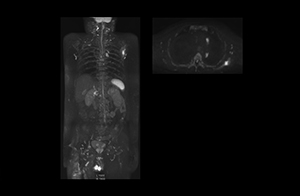

“The DWIBS sequence’s value in oncology cases is due to the high contrast it creates between lesions and surrounding tissue. Whole body DWI is requested by physicians who need to clarify TNM staging or determine therapeutic strategies, oncologists in need of diagnosis or follow-up scans, surgeons who need to see the presence of distant lesions that are sometimes difficult to detect by CT before surgery, and urologists for the evaluation of bone lesions, and the effect of chemotherapy and radiotherapy.”

After implementing the improved whole body protocol, the radiology team initially did not see a large increase in referrals, although Dr. Nobusawa saw clinical cases where the DWIBS images provided him valuable information for diagnosis. This is why Dr. Nobusawa and Mr. Naka started to actively educate referring physicians about the value of whole body DWIBS. They organized several presentations for physicians in the hospital, where they explained how DWIBS can be of value in oncology patients. The information it provides can be useful for physicians when staging cancer, as well as when determining or adjusting treatment strategy. Mr. Naka remembers some cases where DWIBS provided remarkable information. “In one example, DWIBS visualized bone lesions that could not be seen on PET or SPECT. In another case we had found a bone lesion when a normal L-spine scan for narrowing of the disk space was done. One extra DWIBS scan (2 stations, 8 minutes) demonstrated a lesion that later was confirmed to be the primary region of cancer.”